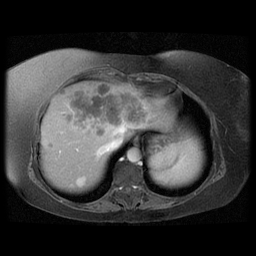

![]() |

| (a) | (b) | (c) | (d) |

Unsupervised Categorization: Our category discovery clusters are generally visually coherent within the cluster and size-balanced across clusters. However, image clusters formed only based on text information (of radiology reports) are highly unbalanced [49], with three clusters inhabiting the majority of images. Note that our method imposes no explicit constraint on the number of instances per cluster. Fig. 6 shows sample images and their top-10 associated key words from two randomly selected clusters (more results are provided in the supplementary material). The LDPO clusters are found to be clinically or semantically related to the corresponding key words, which describe presented anatomies, pathologies (e.g., adenopathy, mass), their associated attributes (e.g., bulky, frontal) and imaging protocols or properties.

The category discovery clusters employing our LDPO method are found to be more visually coherent and cluster-wise balanced in comparison to the results in [49] where clusters are formed only from text information ( radiology reports). Fig. 7 Left shows the image numbers for each cluster from the AlexNet-FC7-Topic setting. The numbers are uniformly distributed with a mean of 778 and standard deviation of 52. Fig. 7 Right illustrates the relation of clustering results derived from image cues or text reports [49]. Note that there is no instance-balance-per-cluster constraints in the LDPO clustering. The clusters in [49] are highly uneven: 3 clusters inhabit the majority of images. Fig. 6 shows sample images and top-10 associated key words from 5 randomly selected clusters (more results in the supplementary material). The LDPO clusters are found to be semantically or clinically related to the corresponding key words, containing the information of (likely appeared) anatomies, pathologies (e.g., adenopathy, mass), their attributes (e.g., bulky, frontal) and imaging protocols or properties.